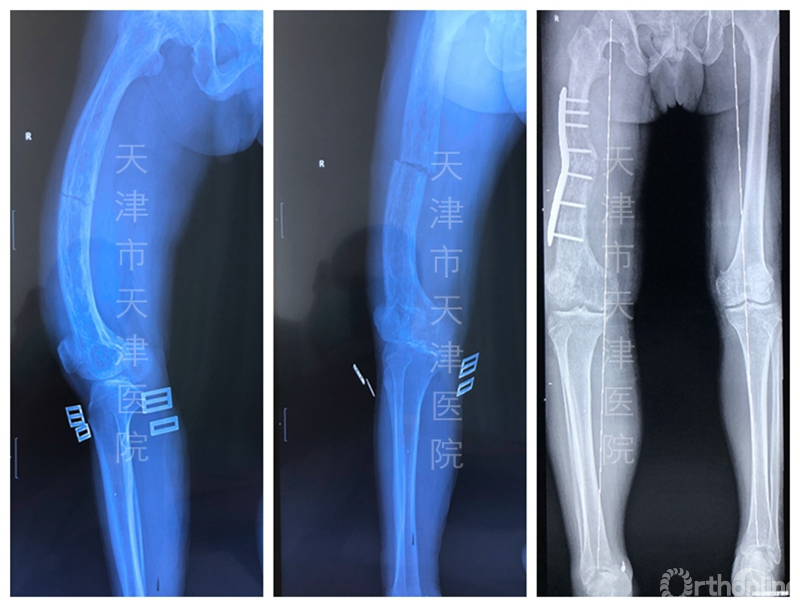

6月初,一位60多岁的paget病(畸形性骨炎)患者发生病理性骨折,患者股骨畸形且粗大,骨皮质变薄,骨小梁稀疏,患肢短缩近6厘米。通常,下肢骨折采用髓内钉固定治疗,但是并没有适合此例患者如此弯曲股骨的髓内钉,那么如何选择治疗方案,是进行外固定治疗还是保守的骨牵引治疗呢?

针对这一问题,马信龙教授团队通过进行低剂量CT分析,复位观察患肢骨折部位原来的畸形形态,决定通过畸形矫正的原则一并解决其骨折和畸形问题。

为此,他们在术前经过数字技术反复模拟设计个性化手术方案,为了对骨折端精准截骨,专门设计了两个个性化截骨导板,分别在骨折端远端和近端完成截骨,然后进行整体复位和个性化钢板固定。在治疗骨折的同时矫正了畸形,术后患肢仅比健肢短1厘米,达到了很好的治疗效果,减轻了患者的痛苦。此类手术已经陆续开展了200余例,均达到了良好的手术效果。

一例Paget's病合并病理性骨折患者术前术后影像片

这种手术对医生是巨大的挑战,但对患者而言是一举两得的好结局。目前,天津医院版个性化手术方案不仅在本院临床应用,还为国内其他医院进行手术方案规划,设计截骨导板和导向器,造福更多患者。